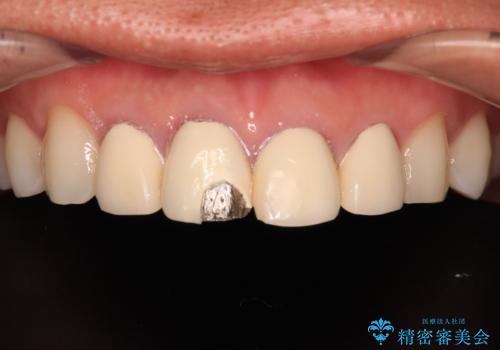

- 以前他院で治療を行った前歯の被せものが欠けてしまい、きれいなセラミックにしたいと来院された患者様です。

人工物のような印象が強くあまり自然とは言えない状態でした。

また被せものと土台の間に隙間があり、適合もよくない状態でした。

根管治療のやり直しは希望されなかったため、土台のやり替えと、より自然なオールセラミッククラウンへのやり替えを行いました。